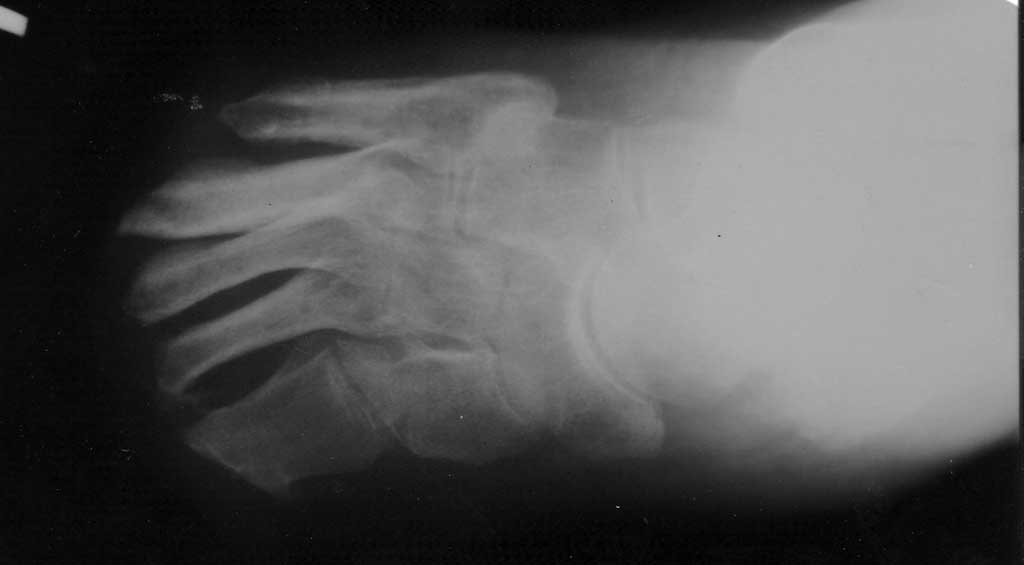

Re: трофическая язва после отморожения

фото

Последнее сообщение хоть и резкое , но не лишено рационального зерна! Если же предположить , что перед нами адекватный человек, то план лечения примерно такой! Сначала (как Вы сказали) выполнить все некрэктомии, в том числе опилить торчащие кости так, чтобы скрыть их под слоем грануляций, затем "вырастить" эти самые грануляции (судя по снимку они атрофичные). Это можно сделать , применяя ГБО, озонотерапию, фарм препараты (напр., актовегин), и, вообще , любые доступные средства и способы , которые активизируют метаболизм в тканях! Как только грануляции "созреют" то предпочтительнее использовать полнослойный кожный трансплантат. Применение трансплантата на питающей ножке не реально у такого пациента.